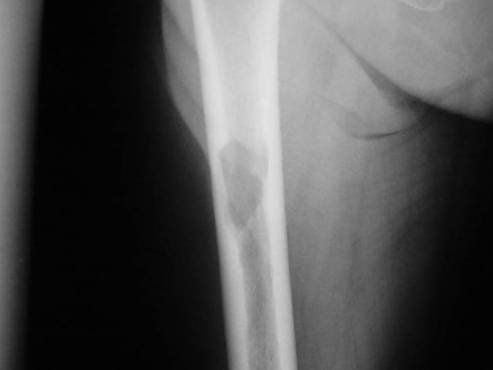

Костная патология

Миелома поражает ребра, позвоночник, тазовые кости, грудину. Появляются опухоли, случаются переломы. Перелом может случиться просто от сильного нажатия на кость. 90% пациентов страдают от болей. Позже человек начинает с трудом двигать конечностями, испытывает сложности при поворотах. На ребрах, черепе и других костях появляются заметные опухолевые узлы. Возникает остеопороз.

Применяется чаще всего при переломах костей.